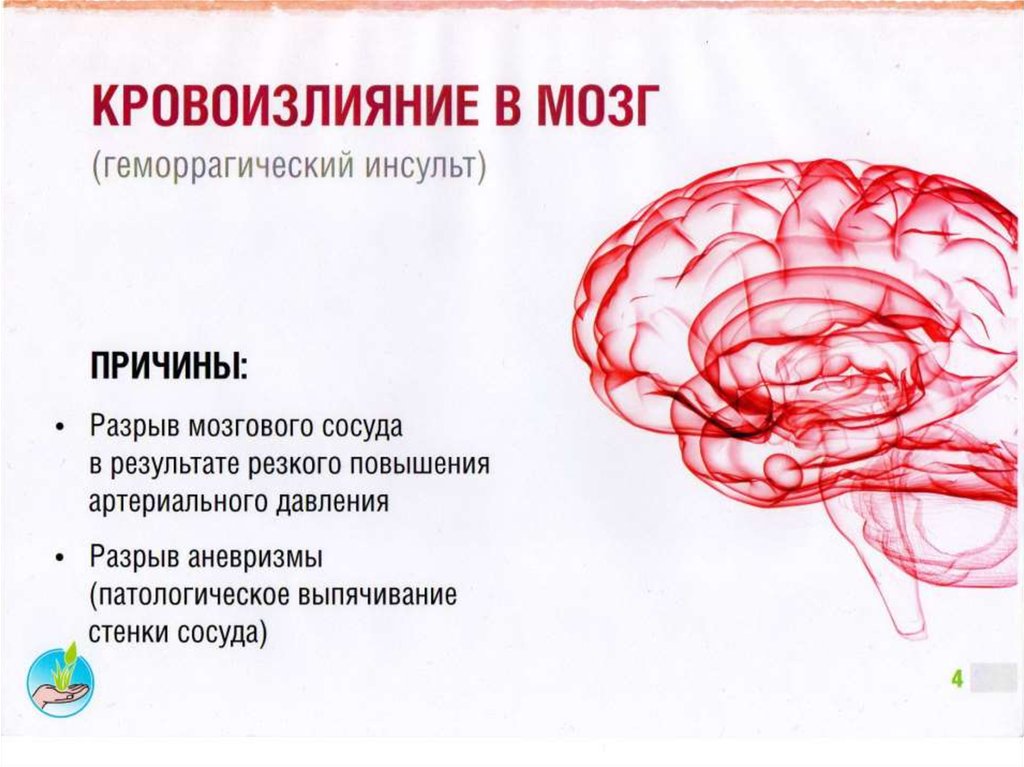

Ишемический инсульт левой стороны: симптомы и реабилитация